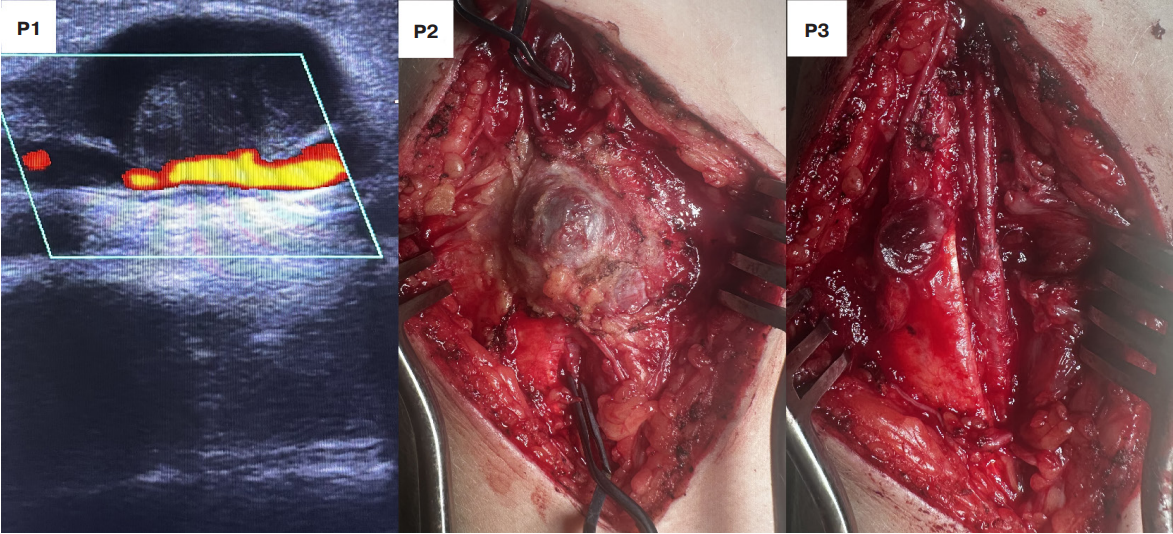

Следует учесть, что единственная псевдоаневризма лучевой артерии являлась наименьшей во всей выборке и составляла 2 см в диаметре. По данным УЗИ определялся дефект стенки артерии, при этом сама полость аневризмы практически полностью тромбирована (рис. 8).

В данной ситуации показанием для оперативного лечения стала нейропатия лучевого нерва, возникшая в результате сдавления. Псевдоаневризма удалена, полипропиленовой нитью 7/0 выполнен анастомоз лучевой артерии по типу "конец-в-конец" (рис. 8). Послеоперационный период протекал без особенностей. Симптомы нейропатии регрессировали на 20 сут. после вмешательства.

Рис. 8. Оперативное лечение псевдоаневризмы лучевой артерии.

Примечание: Р1 — ультразвуковой снимок псевдоаневризмы; Р2 — псевдоаневризма лучевой артерии после выделения; Р3 — реконструкция лучевой артерии анастомозом "конец-в-конец".